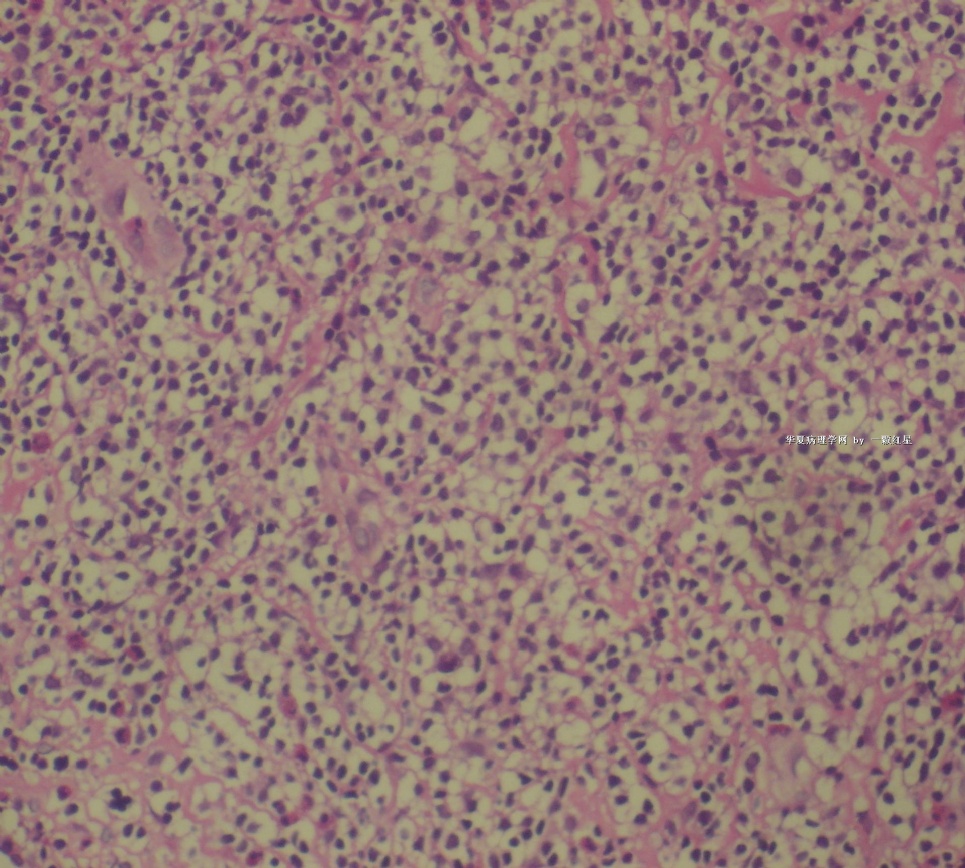

姓    名: ××× 性别:  女 年龄:  77岁

标本名称:  左前臂数个大小不等的皮下肿物。

既往有非何杰金淋巴瘤(滤泡性淋巴瘤)病史22个月。

• 左前臂数个大小不等的皮下肿物     淋巴瘤?图4

图4

病例不错。细胞胞浆透亮,间质血管丰富,图片不是很清晰,似乎有嗜酸粒细胞?

恶性,首先考虑T-NHL。IHC证实。

既往有NHL病史,图片不太清晰,细胞弥漫,胞浆透亮,首先考虑T细胞淋巴瘤。